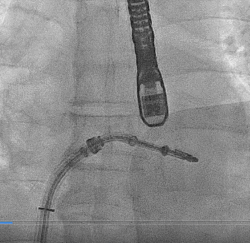

患者全麻以后,在经食道超声心动图和X射线引导下,经股静脉入路,将MitraClip瓣膜夹顺利送至二尖瓣前后叶交界中心处,成功捕捉二尖瓣前叶A2和后叶P2,经超声心动图反复确认瓣叶夹持牢固后,测定有效夹持长度10.4mm,评估反流量降至轻度,释放瓣膜夹,超声心动图评估瓣膜夹位置和功能良好,测定左房压降至26/12mmHg,再次评估反流量仍为轻度,手术顺利完成。

▲ MitraClip释放

王焱、王斌教授团队通过术前和台北荣民总医院(Taipei Veterans General Hospital)宋思贤教授进行了详细的讨论并制定了最优的手术策略,同时术中视频连线获得宋思贤教授的技术支持,主播福利 超声内科苏茂龙教授负责术中超声心动图引导。患者全麻以后,在经食道超声心动图和X射线引导下,经股静脉入路,将MitraClip瓣膜夹顺利送至二尖瓣前后叶交界中心处,成功捕捉二尖瓣前叶A2和后叶P2,经超声心动图反复确认瓣叶夹持牢固后,测定有效夹持长度11mm,评估反流量降至微量,释放瓣膜夹,超声心动图评估瓣膜夹位置和功能良好,测定左房压降至11/6mmHg,再次评估反流量仍为微量,手术顺利完成。